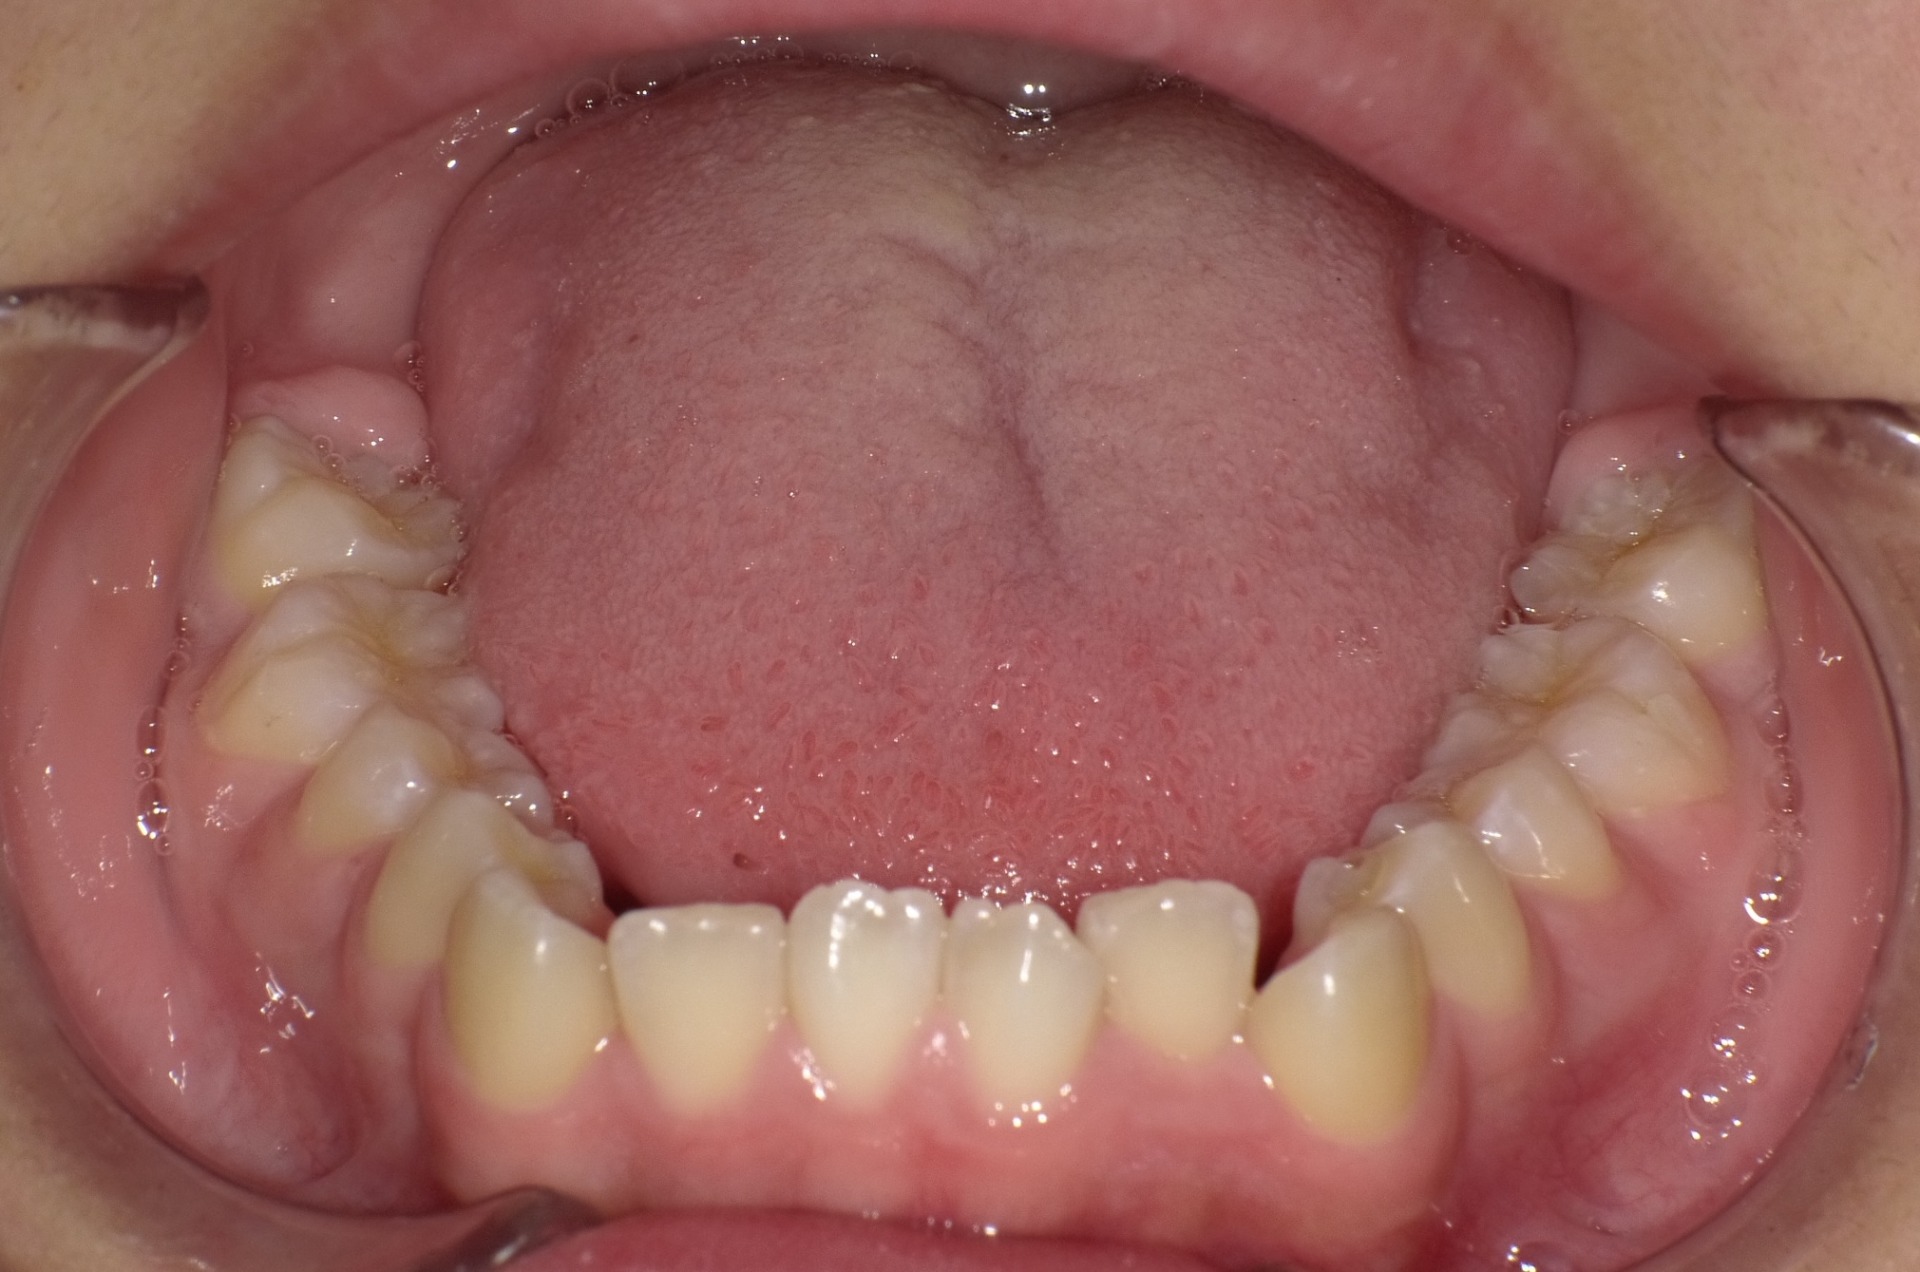

途中経過